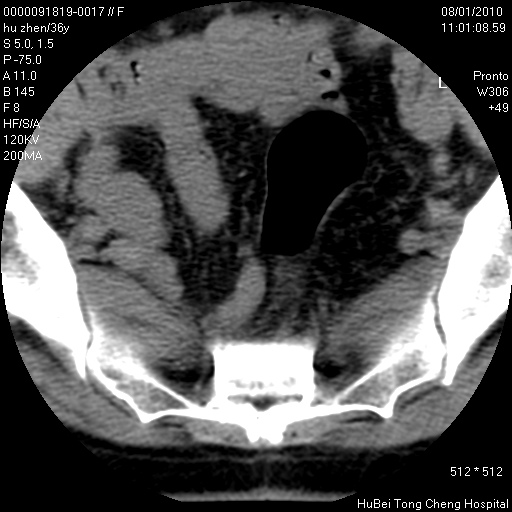

患者 女,36岁。右侧腰腿痛半月余。腰骶椎mr平扫偶然发现骶椎异常信号。

临床诊断:1)腰椎间盘突出症。2)骶椎肿瘤性病变?

骶椎ct平扫(层厚、层距均为5mm),图像如下: